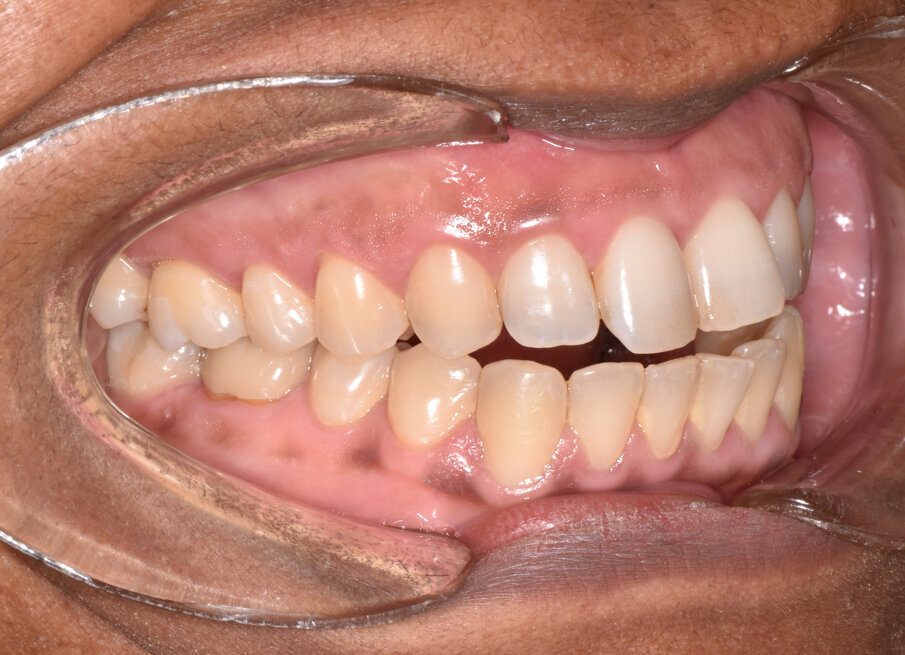

A 56-year-old female patient presented with a Class III malocclusion, anterior crowding and a 2-3 mm anterior open bite. Clinical photographs showed an ideal incisor display upon smiling. The panoramic film was unremarkable, and the lateral cephalometric film revealed a negative 1 mm overjet. (Figs. 1 to 10)

The patient’s chief complaint was the anterior open bite, which she stated caused difficulty in chewing. She expressed unwillingness to wear braces or have TADS placed.

The 31-aligner Spark treatment concluded in five appointments over 7.75 months of active treatment without the need for TADS or refinement aligners. The patient’s excellent compliance was an important factor in the results achieved. Post-treatment photographs demonstrate correction of her Class III, crowded, anterior open bite malocclusion. (Figs. 16-23)